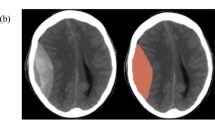

Basal Cistern Measurements

Independently, two investigators (A.Y., R.P.), not involved with data collection and blinded to the patient’s condition, measured the basal cisterns on from the initial admission CT head. All CT scans were performed with a basic non-contrast protocol using a 16-slice scanner (Somatom Sensation 16 scanner; Siemens Healthcare, Erlangen, Germany). Each observer scrolled through the CT head slices to visualise the specific imaging cut demonstrating a visual estimation of the greatest width. The image window was configured to the ‘brain’ view which yielded the basal cisterns in more detail (Hounsfield unit range, 25–40). The image was then magnified and the cisterns were measured using electronic callipers, with a digital viewer (Centricity PACS; General Electric Healthcare, Little Chalfont, UK) (Fig. 1).

The median ICP was 15.2 (IQR, 12.7–19.2) with a median PRx −0.02 (IQR, −0.18 to 0.14). Baseline CT features included subarachnoid haemorrhage in 31% of patients and midline shift in 63% of patients. Forty-four percent were observed to have a focal lesion in the form of a contusion of an extra-axial haematoma. Fifty-six percent of patients suffered diffuse axonal injury (DAI). Taking a threshold of <2 mm as “compressed basal cisterns”, it was observed that on days 1 and 2 of monitoring there was no significant correlation between compression of the basal cisterns and ICP. Only on day 3 of monitoring was there a significant difference in ICP between open basal cisterns (16.2 mmHg) compared to those that were compressed (20.1 mmHg; p = 0.004; Fig. 1). With regards to PRx, compressed basal cisterns trended towards impaired PRx; however, this never reach significance. Interestingly, evidence of subarachnoid haemorrhage on CT was associated with raised ICP on days 2 (20.3 mmHg) and 3 (19.8 mmHg) compared to those who did not (14.2 mmHg and 14.9 mmHg) on days 2 and 3 respectively (Fig. 2). Finally, features of midline shift were not associated with deranged ICP or PRx (p = 0.62; Fig. 3).